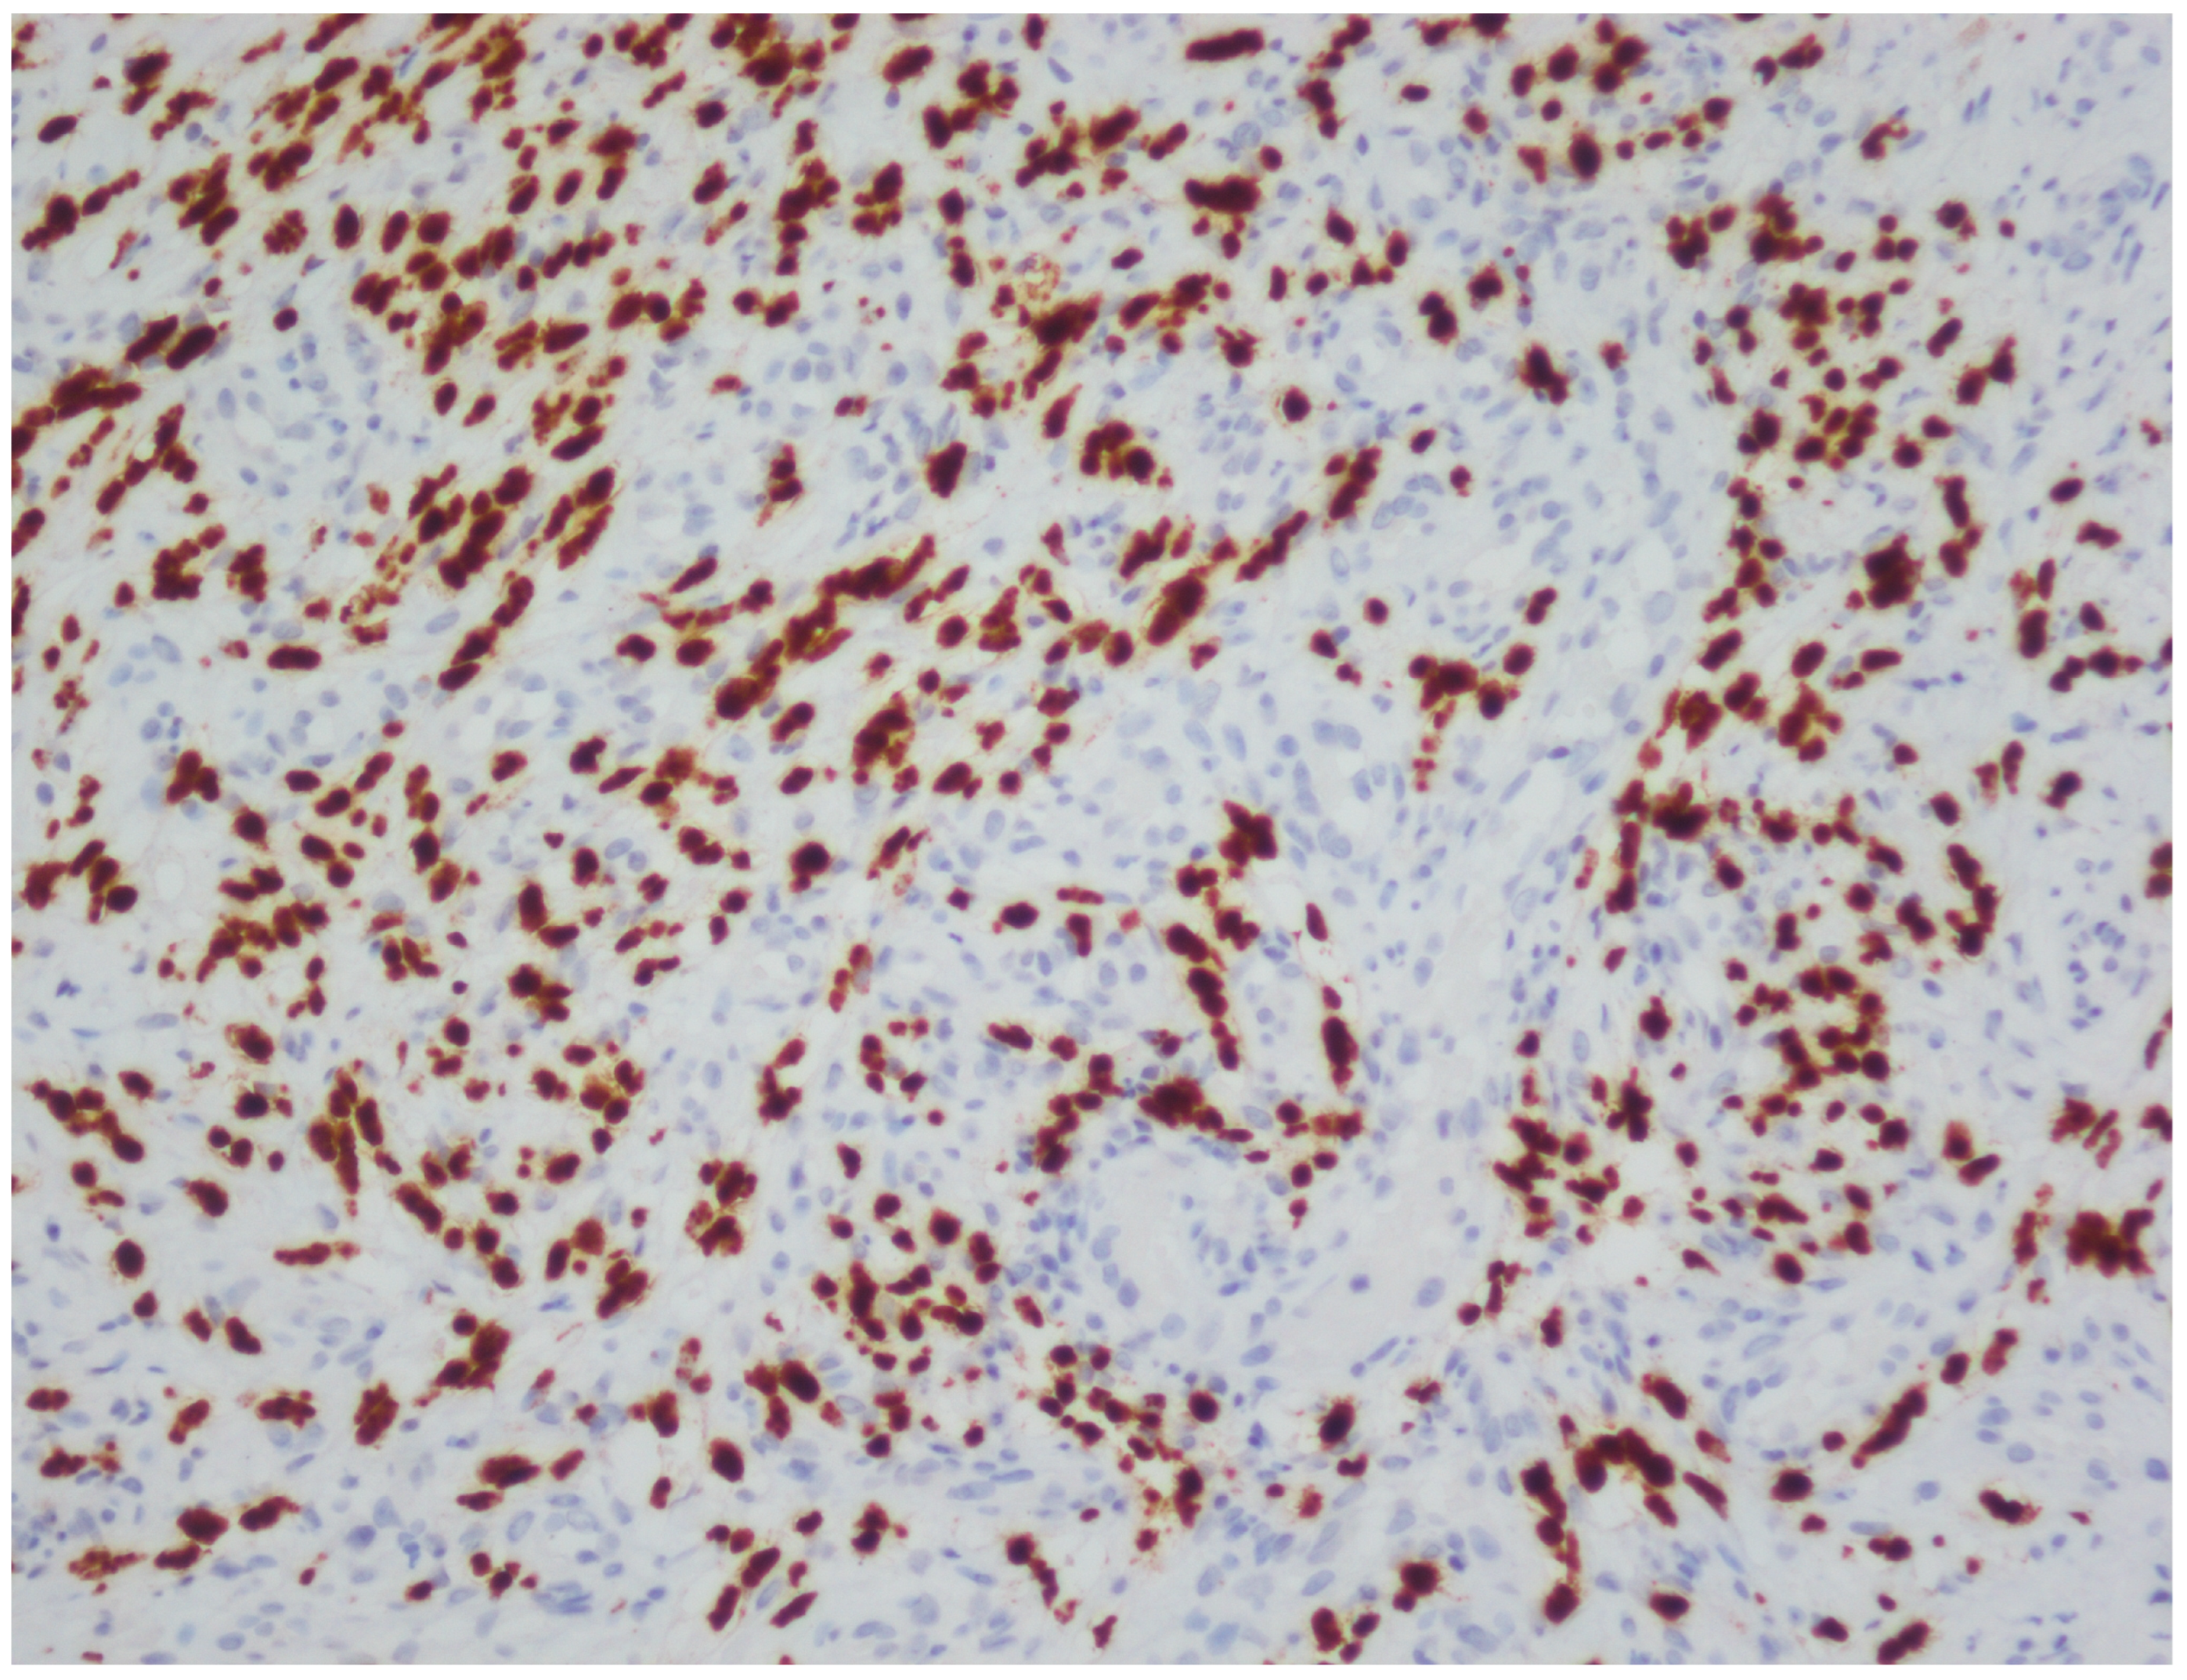

2.5. Histopathological Processing and Immunohistochemistry

| LANA | Latency-associated nuclear antigen |

| DAB | 3,3′-diaminobenzidine |